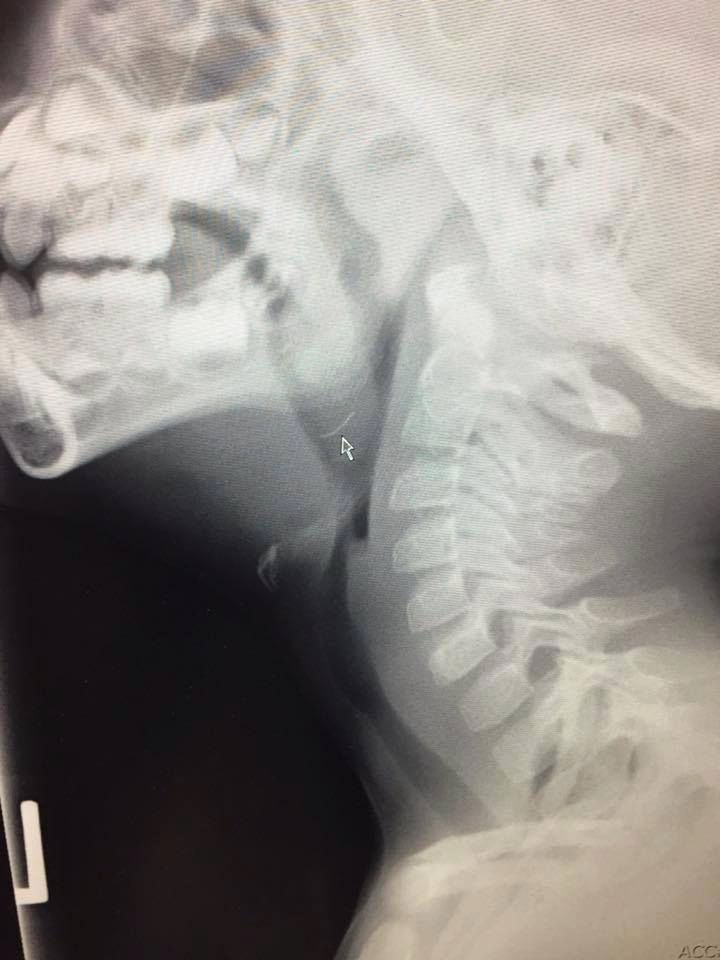

Metalowe elementy szczotki czyszczącej! Okazało się, że kolejne kawałki kurczaka też je miały. Zrobione po dwóch godzinach prześwietlenie mojego synka potwierdziło nasze obawy. Ollie nie mógł przełykać!

Mały Ollie połknął kawałek metalu

Mały Ollie połknął kawałek metalu © Facebook @Jenna Kuchik